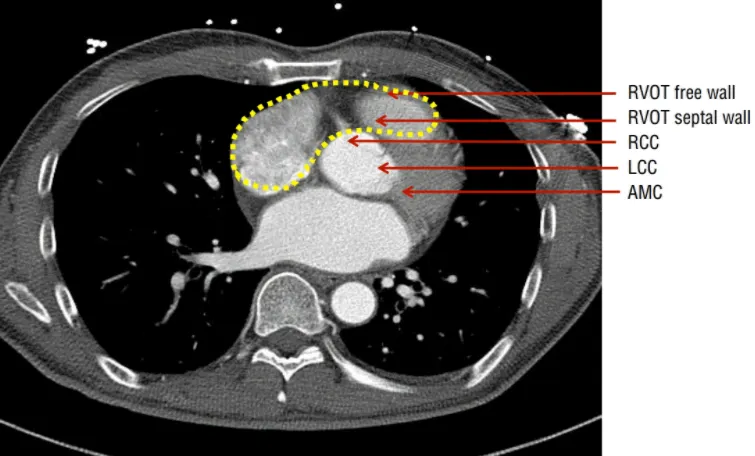

(2) 유출로의 해부학적 특징

RVOT는 LVOT에 비해 좌측 및 앞쪽 방향에 위치

pulmonic valve는 aortic valve의 위쪽에 위치

RVOT는 muscular infundibulum으로 싸여있다.

LVOT는 근육과 섬유(fibrous)로 이루어져 있다.

Aortic sinuses of Valsalva의 오른쪽 대부분과 외쪽의 일부분 은 LVOT를 덮고 있고, AV node, His bundle에 가까이 있다.

임상적으로 septal RVOT와 자유벽(free wall) RVOT는 전방, 중앙, 후방으로 구분할 수 있다

Anteroseptal RVOT는 LV epicardium 근처 interventricular vein 앞쪽에 있다.

Posteroseptal RVOT는 RCC 근처에 있으며, RVOT VT는 주로 anteroseptal RVOT에서 발생한다.